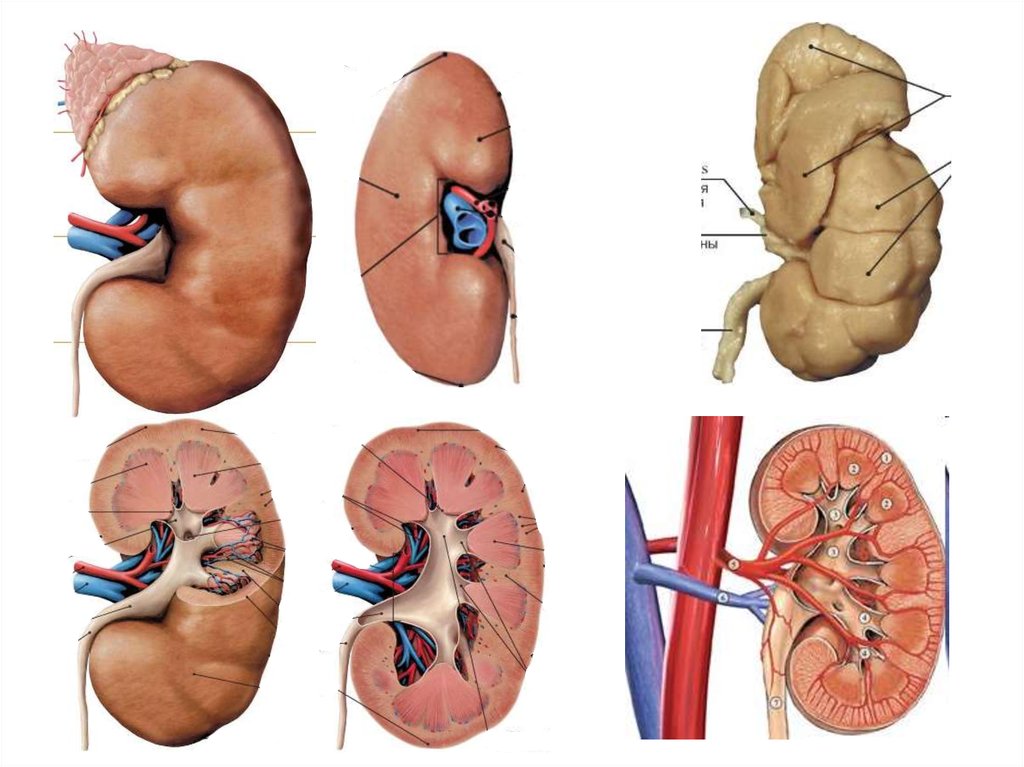

Мочевыделительная система